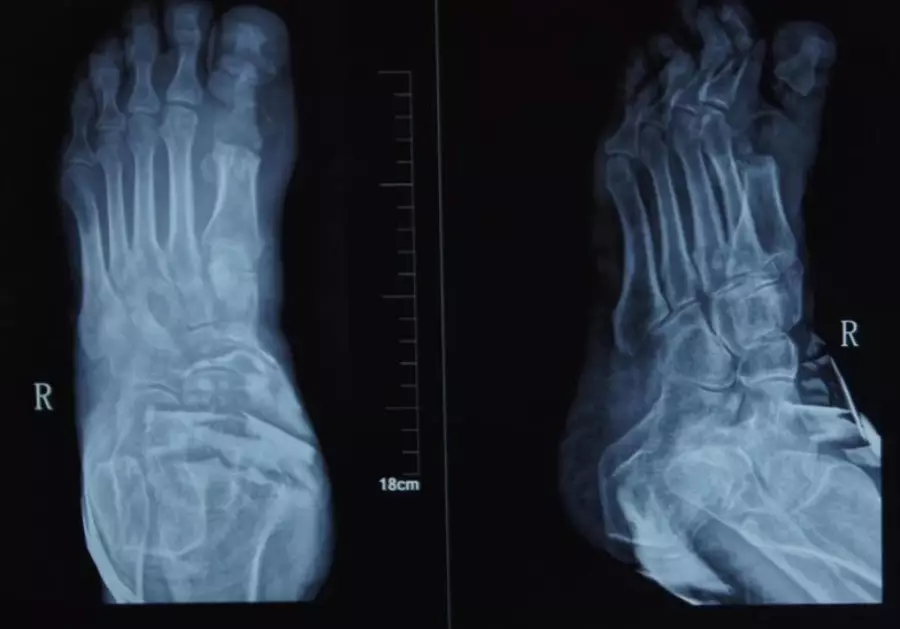

X光片發現少年指骨也出現嚴重感染。網圖

由外科副主任醫師李濤看了X光片後發現,少年的手只不僅皮膚化膿,指骨也出現嚴重感染,必須立刻進行手術,否則可能要截肢,最後清除了所有壞死的骨組織,順利保住了手指。